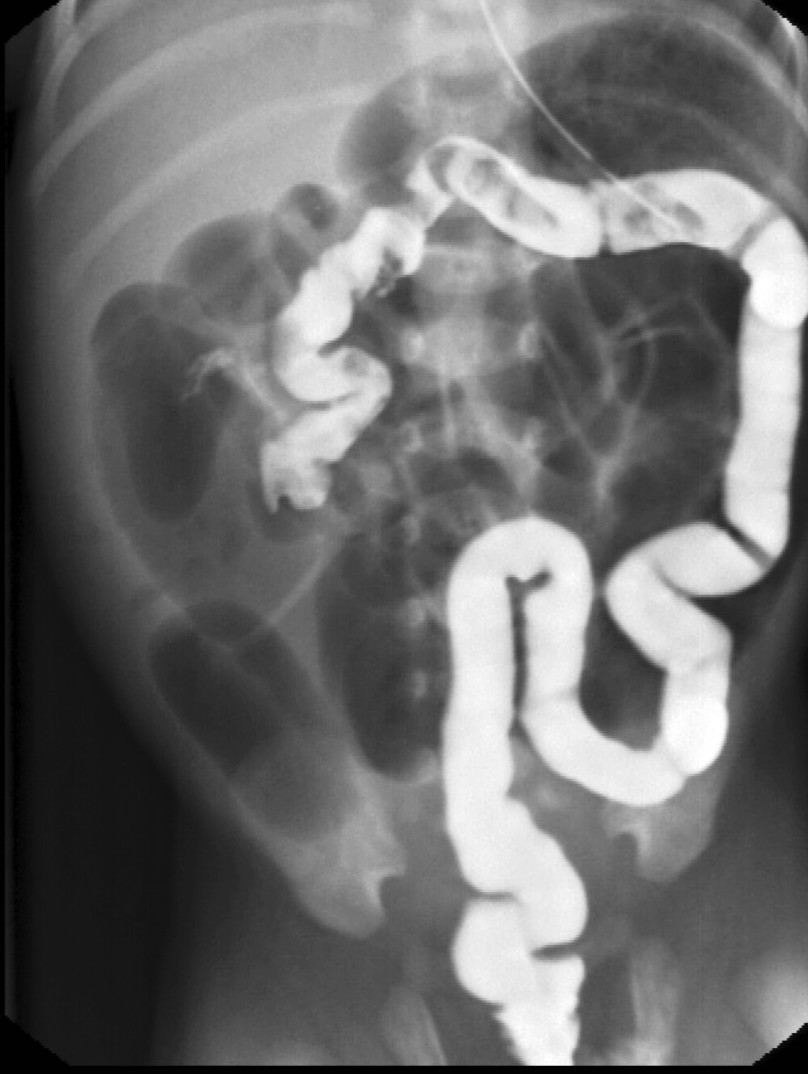

Malrotation-volvulus. During the normal development of the intestinal tract, the intestinal loops make three 90 degree clock-wise rotations around the mesenteric superior artery (MSA.) If this rotation only partially occurs during the embryonic development the intestines remain in a non-rotational or malrotational position, the mesenteric root will be shorter and the cecum will be weakly attached. This anatomic positioning can be symptom free throughout a lifetime, but it predisposes for volvulus. Volvulus can occur at any age, but it is most frequent in the first months of life, when it abruptly occurs with acute bilious vomiting. In this state the intestines around the mesenteric root twist, end up in a complete obstruction that can lead to a rapid death of the intestines. Ultrasonography can depict the mesenteric superior vein (MSV) coiled up around the MSA, so called “whirlpool”-sign.

During X-ray examination the contrast material does not progress to the jejunal loops or it shows a “corkscrew” sign on the right side of the vertebrae as it piles up in the twisted intestinal loops.

Image

15. Contrast material empties the stomach slowly, small intestines are found on the right side of the abdomen. Malrotation-volvulus.